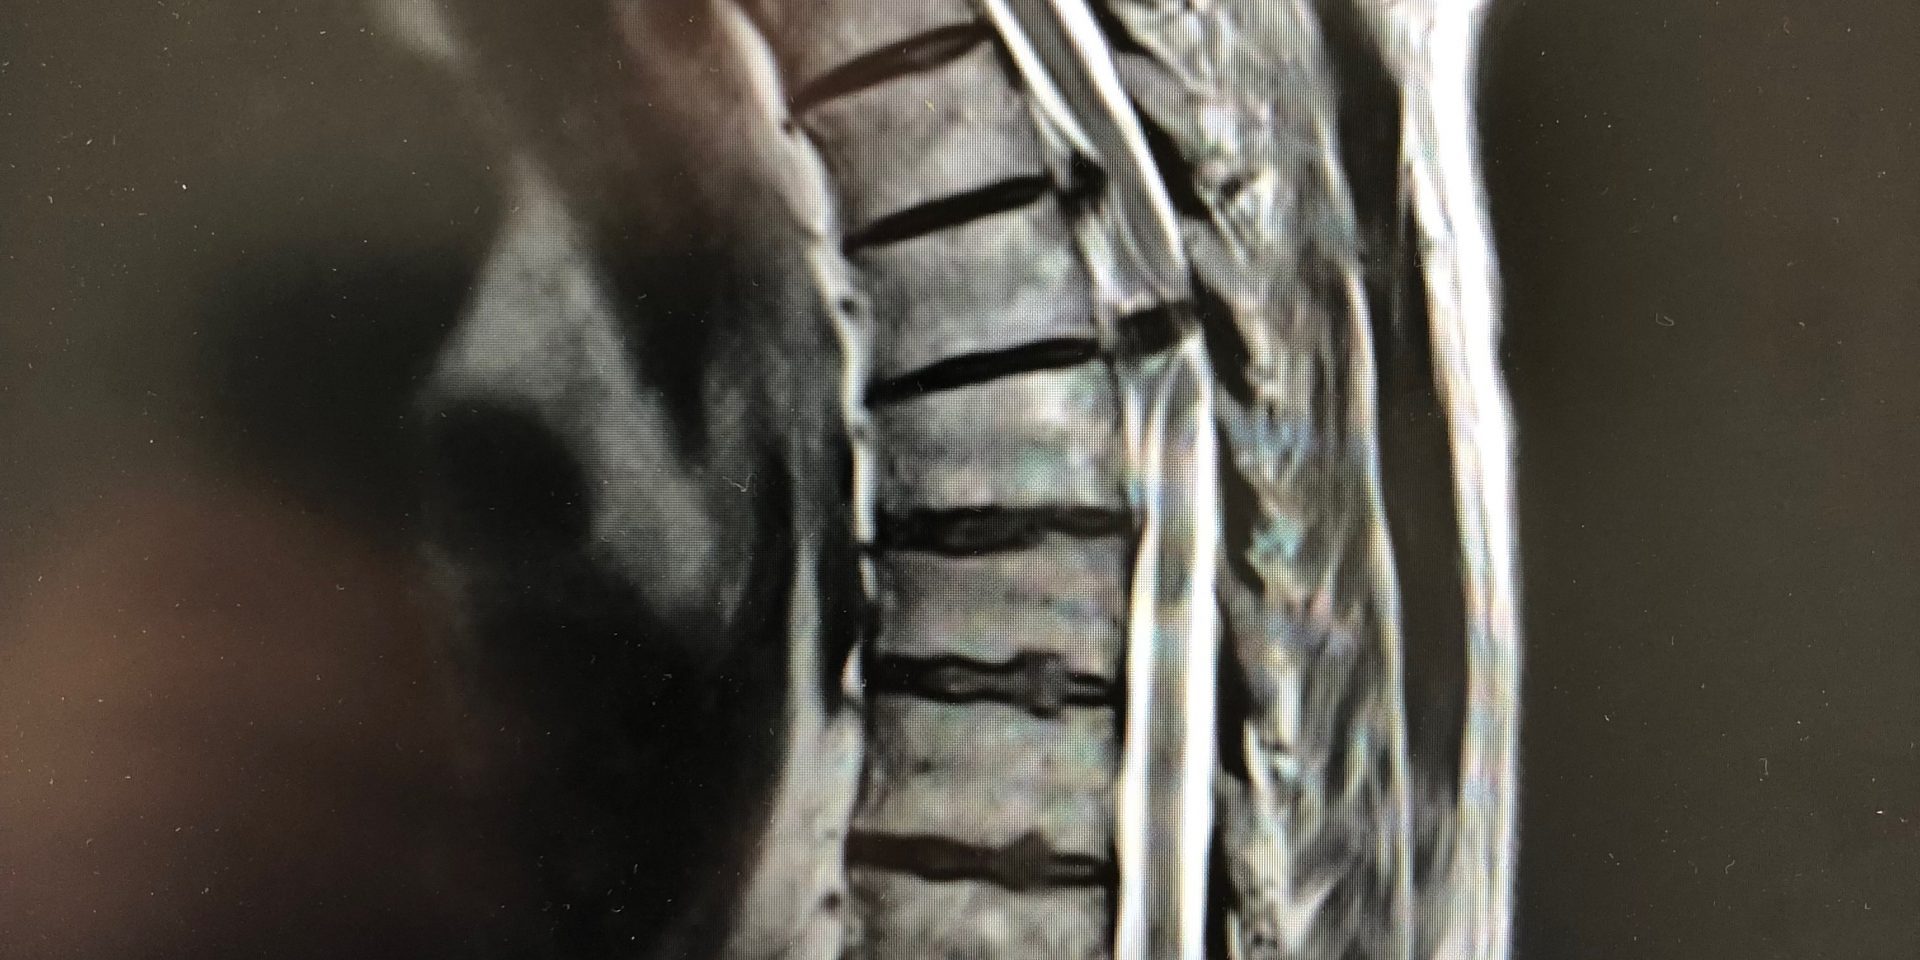

Ο απεικονιστικός έλεγχος ανέδειξε δύο επασβεστωμένες θωρακικές δισκοκήλες στο ύψος Θ6/7 και Θ7/8.

Διενεργήθη διαθωρακική προσπέλαση και μικροχειρουργική αφαίρεση και των δύο δισκοκηλών.